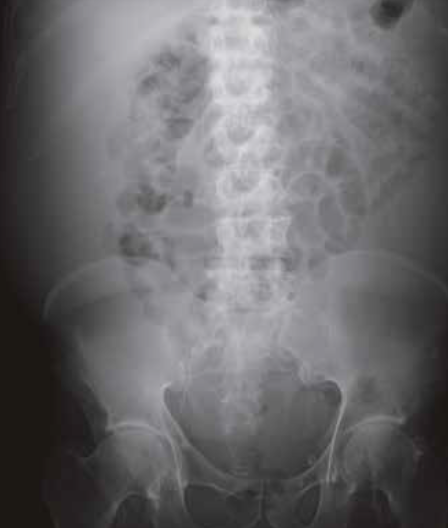

La radiografia diretta dell’addome è una metodica diagnostica semplice, poco costosa e a bassa esposizione radiante. È l’indagine di prima scelta nei pazienti con addome acuto, sospetto di occlusione intestinale o perforazione intestinale, nonché per la ricerca di corpi estranei.

1. Densità ossea a livello della testa femorale.

2. Densità idrica o dei tessuti molli a livello dei muscoli psoas.

3. Densità aerea a livello del gas colico.

La densità adiposa si osserva a livello delle linee che individuano i profili delle strutture anatomiche in esame.

La lettura sistematica di un radiogramma diretto dell’addome è un processo cruciale che segue un metodo costante per non tralasciare alcuna alterazione significativa. Questo metodo si applica anche alla radiologia toracica e richiede un’attenzione particolare alle seguenti strutture:

Ossa

L’esame delle strutture dello scheletro assile inizia dall’alto verso il basso, valutando eventuali alterazioni delle curve fisiologiche del rachide lombare, come la scoliosi, o cambiamenti nella morfologia dei corpi vertebrali, come i crolli somatici. Si devono anche considerare le alterazioni di carattere traumatico, infiammatorio, osteolitico o osteoblastico, come nel caso di mieloma multiplo o lesioni secondarie.

Tessuti molli

La differenziazione tra due strutture con la stessa densità radiologica è possibile grazie allo strato di grasso periviscerale che circonda gli organi parenchimatosi e i muscoli addominali, creando un’interfaccia tra la densità idrica/dei tessuti molli e la densità adiposa. Alterazioni o dislocazioni dei contorni anatomici possono indicare la presenza di patologie come masse o processi infiammatori.

In particolare occorre esaminare:

1. Ombra epatica.

2. Muscolo psoas.

3. Ombra renale.

4. Linea del fianco.

5. Ombra vescicale (mal riconoscibile, a vescica repleta).